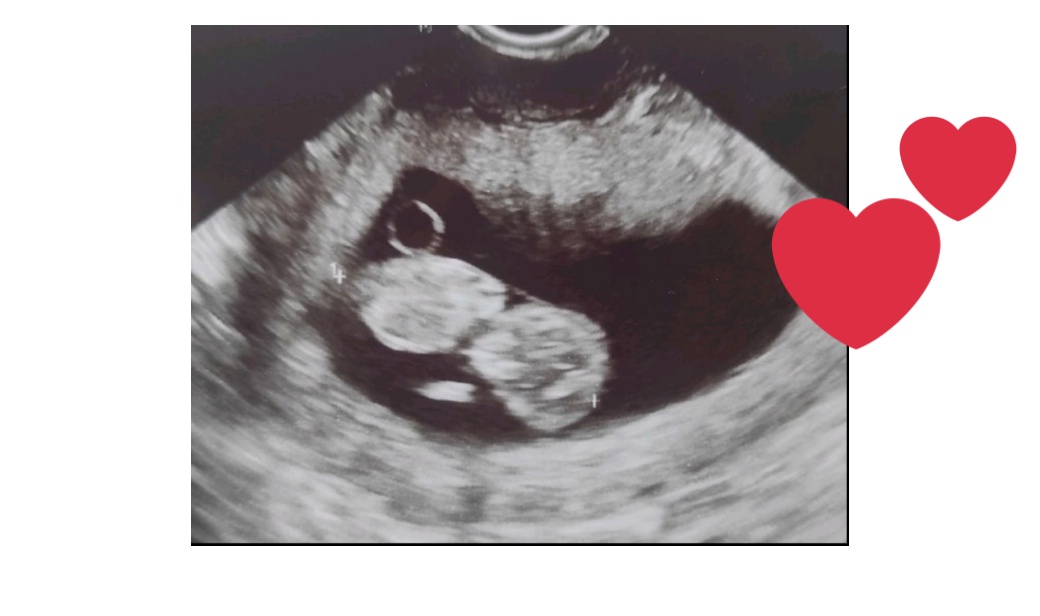

И отново, и отново. Докато... Точно преди 15 дни минах и първа фетална морфология със здраво бебче.